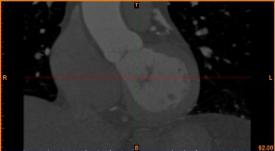

首先通過病人的心臟冠脈造影CT數(shù)據(jù),獲取病人的心臟冠脈三維模型。

病人的冠脈造影CT數(shù)據(jù)                                                                       提取出的冠脈三維數(shù)據(jù)